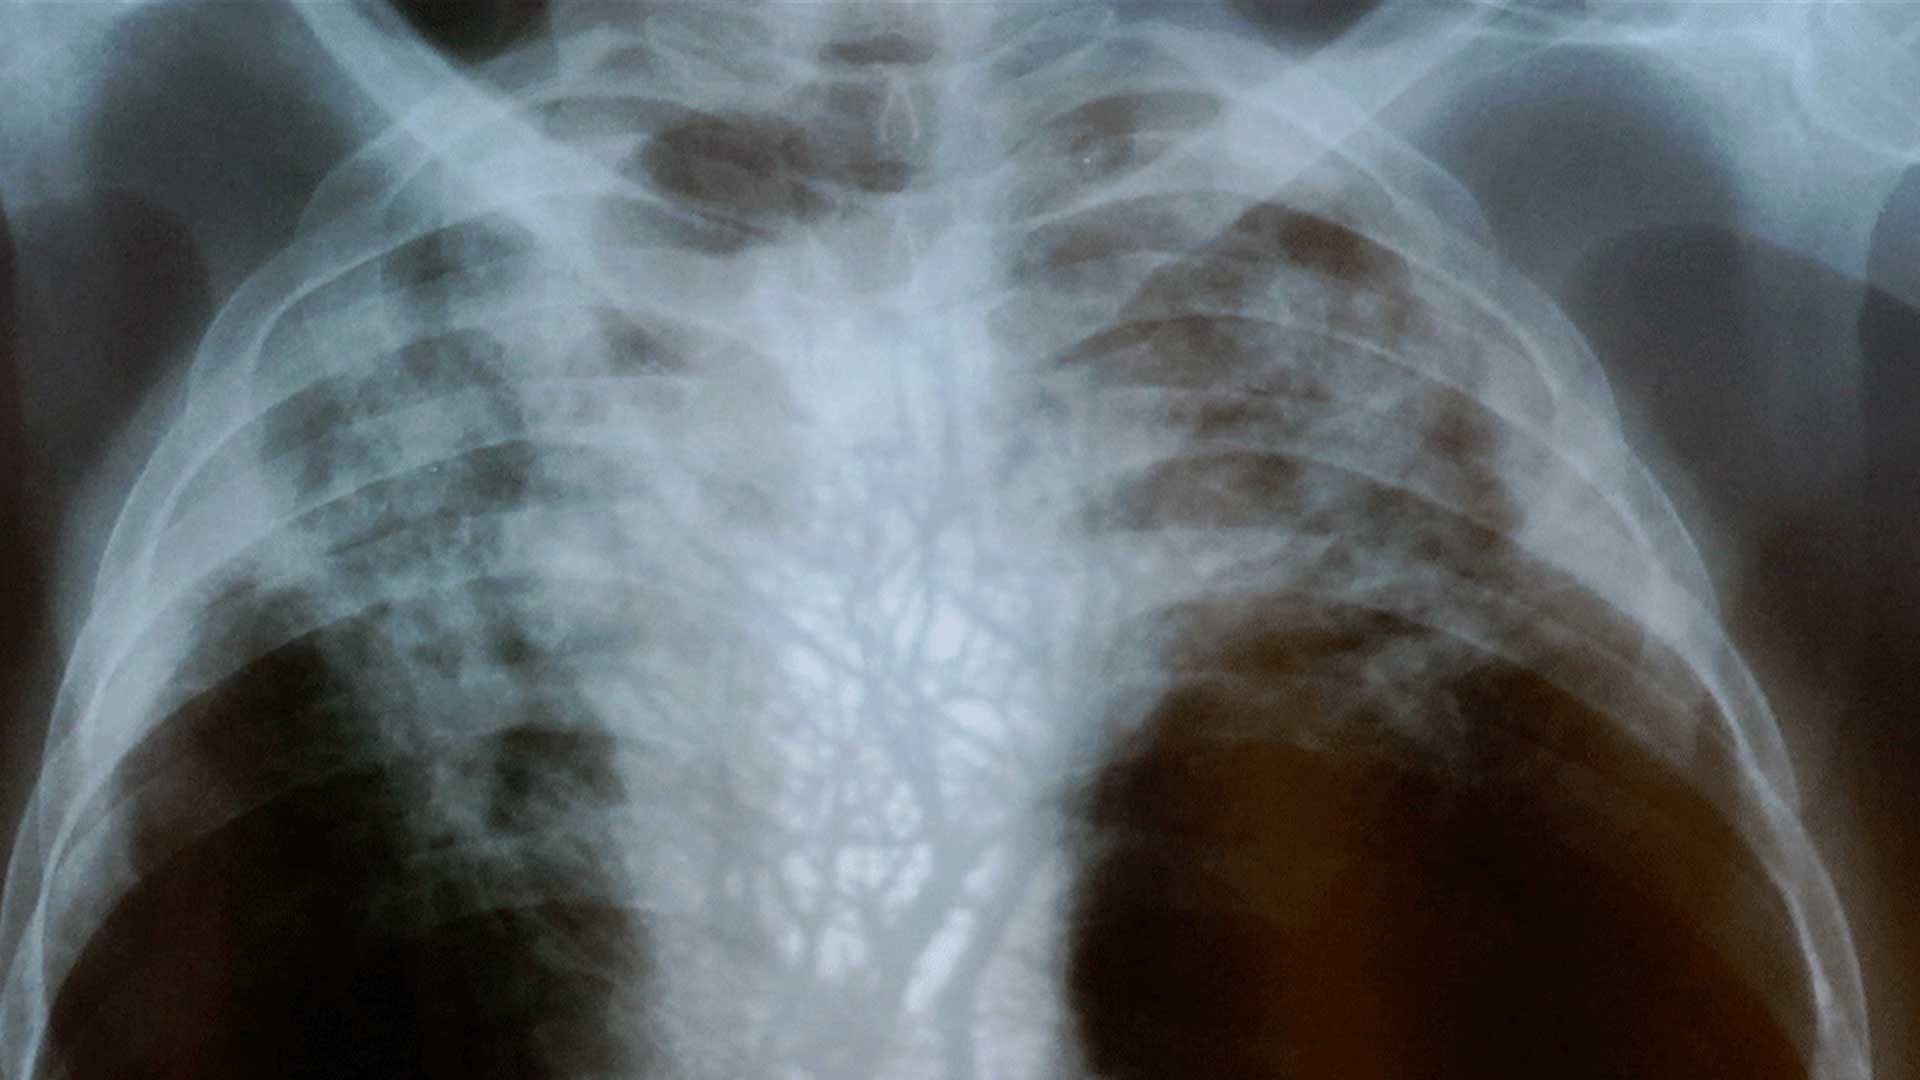

Billed as “the untold story of the making of South Africa”, this devastating documentary explores the numerous ways in which the mining industry was a key force in shaping apartheid South Africa. For more than a century, hundreds of thousands of black men from Sub-Saharan Africa have been leaving their families to dig for gold and produce South Africa’s key source of wealth. Featuring a rich archive of footage from the colonial and apartheid eras, along with interviews with gold miners whose lives have been decimated by silicosis and tuberculosis, the film clearly shows how Southern Africa’s indigenous societies were destroyed in order to create a pool of cheap surplus labour that mined some of the world’s richest deposits of gold at the cheapest possible price.